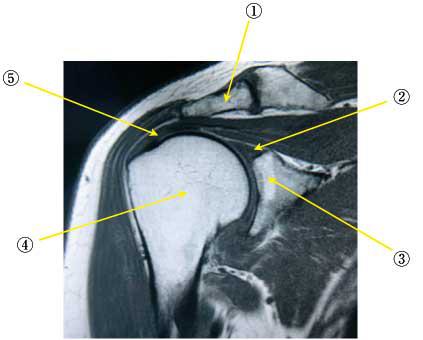

正常な肩関節のMRI(①~⑤)を示す。解剖で誤っているのはどれか。

①鎖骨

②関節唇

③関節窩

④上腕骨頭

⑤腱板